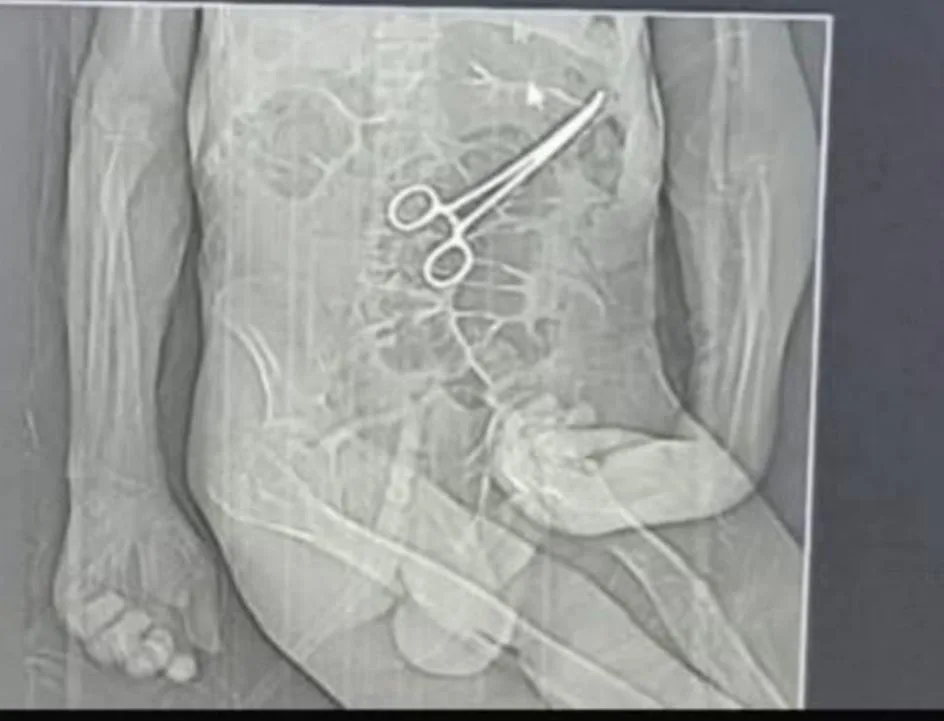

A morte do idoso Manoel Cardoso de Brito, ocorrida após internação no Hospital Municipal de João Pinheiro, tem gerado comoção e levantado graves suspeitas de negligência médica. Familiares e uma cuidadora que acompanhou o paciente relatam falhas no atendimento, ausência de comunicação e a possível presença de uma pinça Kelly,instrumento cirúrgico semelhante a uma tesoura, esquecida no abdômen do idoso após um procedimento cirúrgico.

A cuidadora relata que, posteriormente, foi informada de que o objeto seria uma pinça Kelly, instrumento cirúrgico metálico utilizado para contenção de vasos e tecidos.